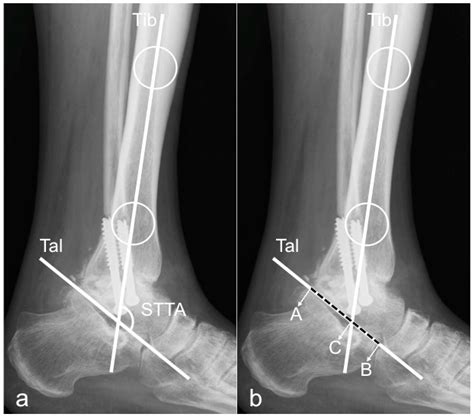

Interpreting a Lateral Foot X Ray

Interpreting a lateral foot X ray requires a trained eye and knowledge of foot anatomy. Here are some key points to consider:

• Bone Density: Assess the density and clarity of the bones. Abnormalities in bone density can indicate conditions like osteoporosis or bone tumors.

• Bone Alignment: Check the alignment of the bones, particularly the calcaneus, talus, and metatarsals. Misalignment can indicate fractures, dislocations, or deformities.

• Joint Spaces: Evaluate the joint spaces for any narrowing or irregularities, which can suggest arthritis or other joint diseases.

• Soft Tissue: Look for any abnormalities in the soft tissue, such as swelling, calcifications, or foreign bodies.